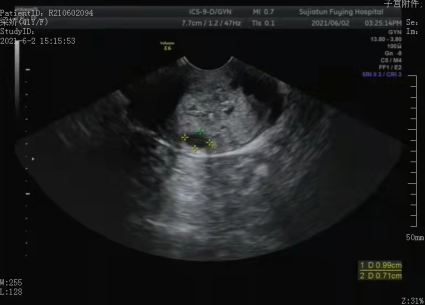

子宫前位,大小约9.6x5.0x5.0cm,子宫内膜厚约1.6cm,回声不均,内见散在小无回声。宫颈形态饱满,见多个囊肿,较大者约1.0x0.7cm,宫颈区彩色血流显示丰富。右附件区见3.4x3.1cm囊肿,形态规整,边界清,内呈无回声。左卵巢大小约2.6x1.7cm,左附件区未见占位性病变。

超声提示:

1、子宫内膜增厚

2、宫颈回声结合临床

3、右附件区囊肿

子宫内膜增厚

宫颈多发囊肿

宫颈可显示较丰富血流信号

患者来就诊时病史不典型,没有接触性出血的病史,代之以不规则阴道流血。超声扫查过程中也没有显示肿块,仅仅是密布的多个小无回声,所以易误诊为单纯的囊肿。

但仔细分析超声表现,这些囊肿大小不均,形态杂乱其间有明显的彩色血流信号,这些征象还是可疑的,是需要提高警惕的,再加上腺癌的发病部位多位于宫颈管内,需要考虑到宫颈腺癌的可能性。这时就需要我们结合其他辅助检查,给临床一个最为准确的参考。